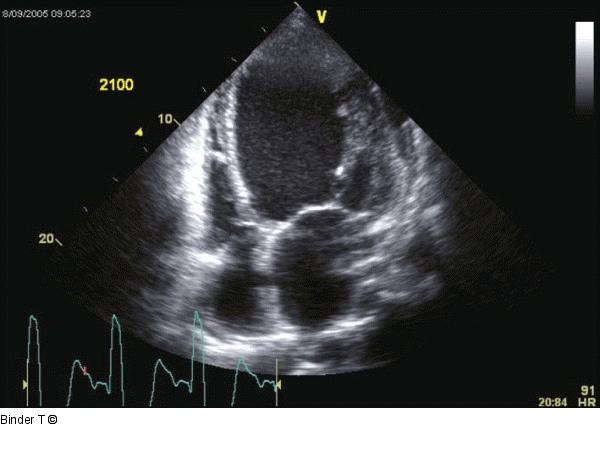

Abbildung 4: Vierkammerblick Deutlich dilatierter linker Ventrikel mit hochgradig reduzierter systolischer Linksventrikelfunktion. Visuell bereits ausgeprägte Dyssynchronie mit biphasischer Bewegung des Septums ("Hula Hoop"- Bewegung des Herzens). Vergrößerter linker Vorhof. Der rechte Ventrikel ist normal groß mit normaler Rechtsventrikelfunktion. Beide Mitraklappensegel sind restriktiv (durch die Dilatation des Ventrikels sind die Klappen Richtung Apex verlagert/gezogen bzw. in ihrer Beweglichkeit eingeschränkt). Kleiner Perikarderguß. |

Abbildung 4: Vierkammerblick

Deutlich dilatierter linker Ventrikel mit hochgradig reduzierter systolischer Linksventrikelfunktion. Visuell bereits ausgeprägte Dyssynchronie mit biphasischer Bewegung des Septums ("Hula Hoop"- Bewegung des Herzens). Vergrößerter linker Vorhof. Der rechte Ventrikel ist normal groß mit normaler Rechtsventrikelfunktion. Beide Mitraklappensegel sind restriktiv (durch die Dilatation des Ventrikels sind die Klappen Richtung Apex verlagert/gezogen bzw. in ihrer Beweglichkeit eingeschränkt). Kleiner Perikarderguß. |